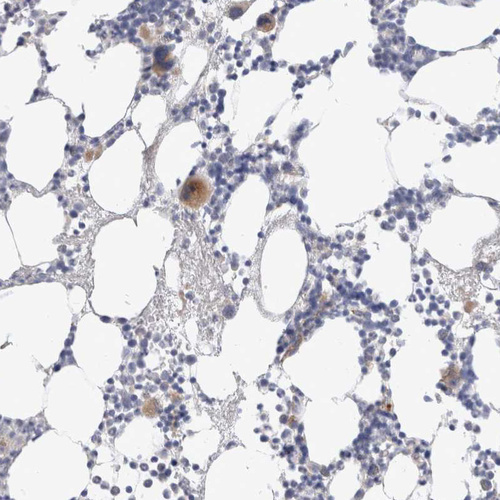

Immunohistochemical staining of human bone marrow shows moderate cytoplasmic positivity in megakaryocytes.